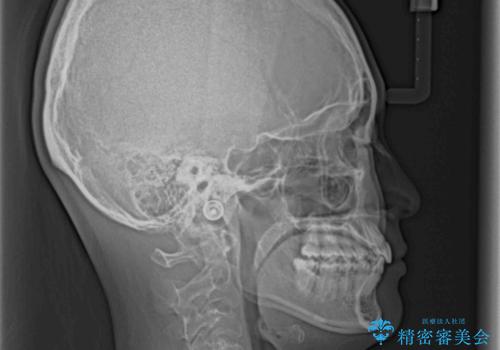

奥歯の倒れた歯を改善 インビザラインでの矯正治療

- 前歯のデコボコと奥歯の不正咬合を気にして来院された患者様です。

左右の大臼歯が全て鋏状咬合(シザーズバイト)になっており、治療が難航することが予想されましたが、インビザラインにより治療を行うこととしました。

最難関と思われたシザーズバイトは比較的短期間で解消されました。

しかし、治療中に2度の出産を経験され、治療期間は長くなってしまいましたが、咬みやすく、清掃しやすい歯列を獲得することができました。